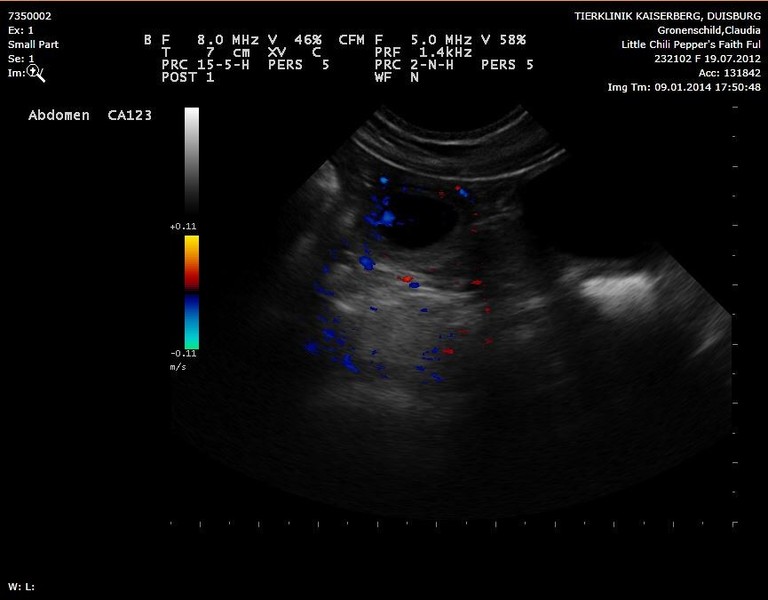

Ultraschallbilder vom 10.01.2014.